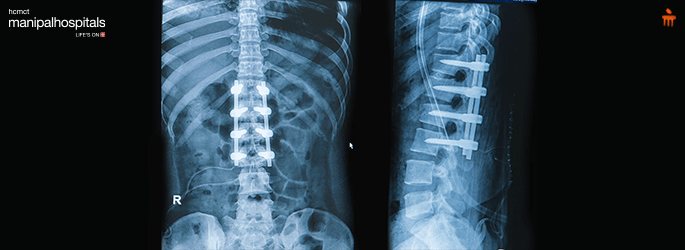

Scoliosis and Kyphosis Deformity Correction Surgery: These are complex surgeries, that are performed to straighten the crooked spine to achieve a balanced and pain-free spine.

Instrumented fusion: Instrumented fusion is a gold-standard surgical procedure for correcting scoliosis deformity. Screws, hooks or wires are put in the vertebrae and slowly connected to rods and with some manoeuvres deformed spine is corrected. A bone graft is then placed over the back of the spinal bones (laminae) to obtain a bony fusion. Fusion simply means fusing two or more vertebrae so that they heal into a single, solid bone and maintain the deformity in the corrected position.